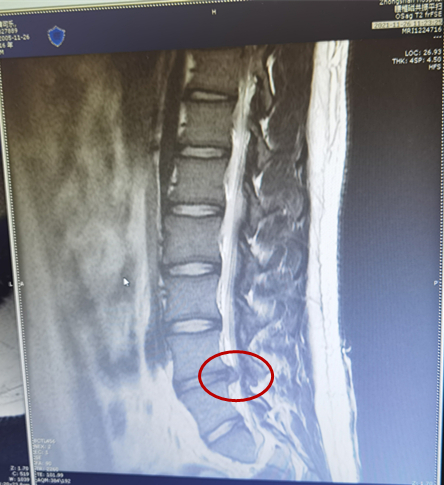

11月30日,抱着最后一丝希望,夫妻俩带着儿子找到了湖北省第三人民医院疼痛科一病区主任王云霞。王主任仔细为患者查体、询问病情,结合核磁共振的结果,王主任判断小王的腿痛是腰椎间盘突出引起的,因为突出有点大,最佳的治疗方案是微创内镜手术。看到李女士的犹豫和担心,王主任对着腰椎片子耐心地解答道:“腰椎间盘突出根据突出的大小、部位及患者的症状可以选择保守治疗和手术治疗,每个患者都有最适合的治疗方案”。“可是他这么小就手术,我还是很担心,会不会不好恢复啊。”李女士仍旧放心不下。

小王的椎间盘突出物

王主任表示,孩子虽只有15岁,但椎间盘突出较大,腿痛腿麻影响睡眠,保守治疗效果不好,如此突出物自行吸收可能性不大,通过微创手术拿出突出物,孩子的腿痛腿麻就会立竿见影好转。王主任介绍,随着科技的进步,腰椎间盘突出症已不再需要传统开刀手术了,这次治疗选择的椎间孔镜微创手术,是在局部麻醉下,经皮穿针经过人体自然孔道椎间孔到达椎间盘突出位置,在内镜明视下清楚的看到神经根与突出物的关系,精准摘除椎间盘突出物,保留有用的椎间盘,达到解除神经根压迫、消除疼痛的效果。整个过程几乎无出血,仅有一个6毫米的小孔,保护了脊柱结构的稳定性不受影响,患者术后24小时即可下床活动。因为损伤小,又是局部麻醉,目前可以说是治疗包括高龄老人、年轻人患腰椎间盘突出症、腰椎管狭窄症的最佳手术方式。